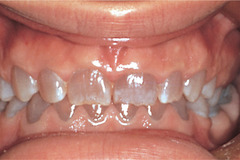

Which tooth development condition is classified by opalescent dentin

Front

Dentinogenesis imperfecta: inherited dentin disorder

Back